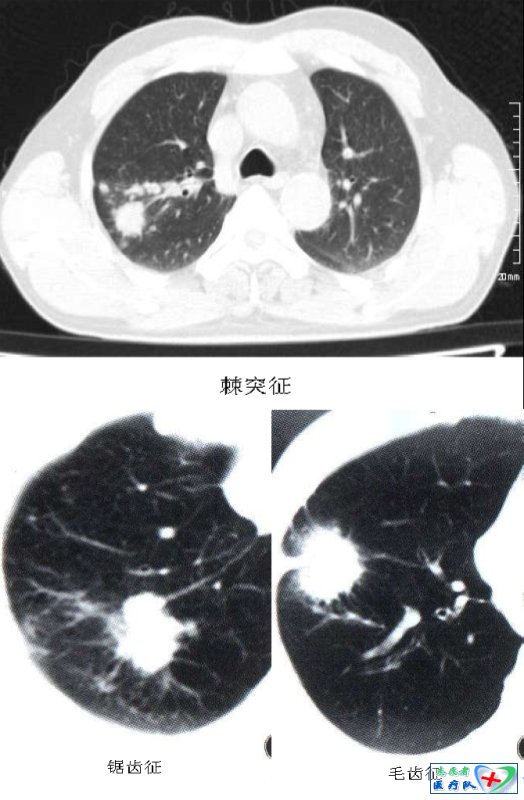

12、棘状突起征(棘突征、锯齿征伪足征):

指结节边缘呈尖角状突起,如同小的三角形,使病灶边缘不规则。如果棘状突起密集排列就构成了“锯齿征”;如果棘状突起粗细、长短不一时,如螃蟹足,就是“伪足征”。上述三种征象其实都是棘突征的不同表现,是介于分叶和毛刺之间的的一种粗大而钝的结构。其病理基础是肿瘤发育先端的浸润性生长,肿瘤因子诱发肿瘤新生血管致使肿瘤组织生长速度不均匀,尤其肿瘤周边部的血管丰富、密度大、数量多(主要来源于支气管动脉,少数来自肺动脉及其他侧枝血管),因而癌细胞增殖活跃;其次,邻近肺组织的瘤巢或肿瘤浸润,使结缔组织水肿、纤维化、增厚等形成棘状突起;第三,肿瘤周围的生长环境如小叶间隔或血管等组织的阻挡作用;另外一种情况是肿瘤突出部分与CT扫描层面部分相切而成尖角状改变。棘状突起也是分叶征的一部分,因此,棘状突起也是肺癌的的重要征象。